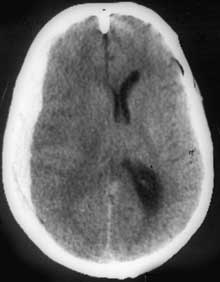

КТ головного мозга. Острая субдуральная гематома в правой лобно-теменно-височной области с дислокацией головного мозга и его сдавлением.